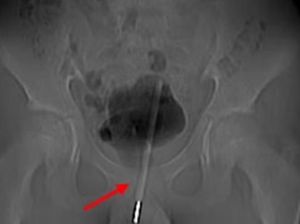

Seorang remaja di China mengalami insiden mengerikan setelah memasukkan termometer ke dalam kandung kemih saat onani. Operasi pun harus dilakukan.